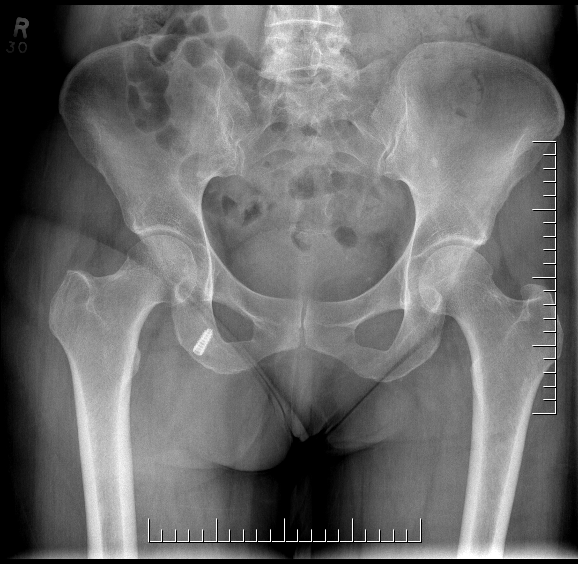

Xray

Exclude bony avulsion

Proximal hamstring tear on right (red circle), normal insertion on tuberosity on left (blue circle)

Proximal hamstring avulsion on right - red circle is retracted hamstring tendon, blue circle is normal insertion on left

Proximal hamstring tear on right (red circle), normal insertion on left (blue circle)